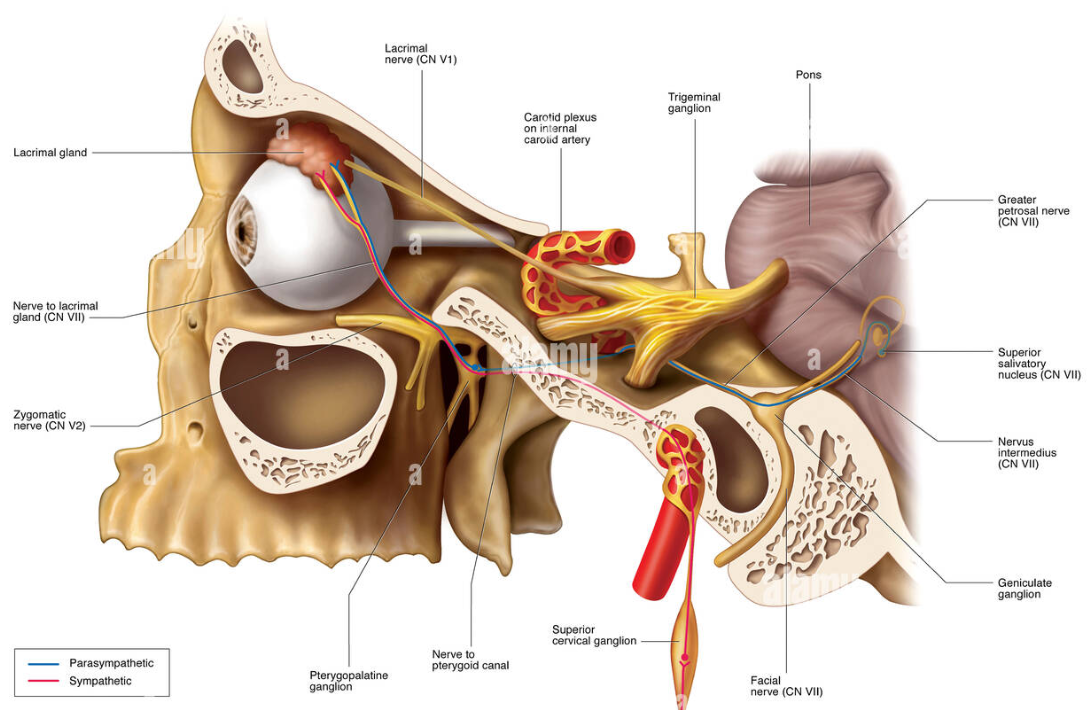

CN VII

-

Greater petrosal n.(Parasymphysis)

- Mucous g.

- Lacrimal g.

Stapedius n.

- 支配Stapedius m.

Chorda Tympanic n.(Parasymphysis)

- 支配前味覺

- Submandibular, Sublingual g.

Sup. cervical ganglion

支配carotid plexus, pharyngeal plexus